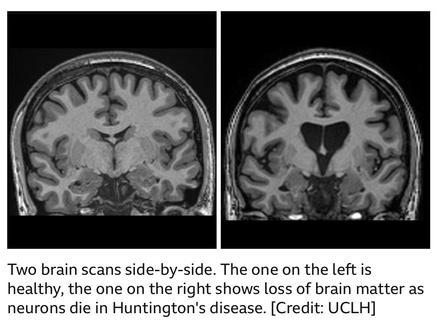

Huntington’s disease is a rare and inherited brain disorder, which is caused by a mutated allele, which produces a toxic protein. This protein then gradually damages cells in the brain - leading to problems with movement, thinking and behaviour. Normally, it begins in mid-adulthood and gradually gets worse over many years.

Scientists at the world-renowned University College London, collaborated alongside the biotech firm uniQure in a monumental development. The team have managed to successfully treat Huntington’s disease for the first time using an experimental gene therapy called AMT-130.

The trial took 3 years, and involved 29 patients. Those who received high doses of the therapy saw the disease progression slow by roughly 75% in comparison to the projected rates. The treatment plan uses a modified virus to deliver a strand of therapeutic DNA into brain cells to suppress the production of the huntingtin protein which is toxic and derives the disease.

To deliver the therapy, a complex method is employed, with the viral vector being infused into 2 regions of the brain over 12-20 hours. Despite there being some side effects such as central nervous system inflammation, which were then treated with steroids, they were mainly linked to the surgery.

For patients, these findings are a landmark in the treatment plan, as Huntington’s was for a long time considered incurable, yet may now be shifted into a treatable condition. UniQure has already taken the steps to bring this to hospitals - planning to seek regulatory approval in the United States in early 2026, and then in Europe and the UK in following years.